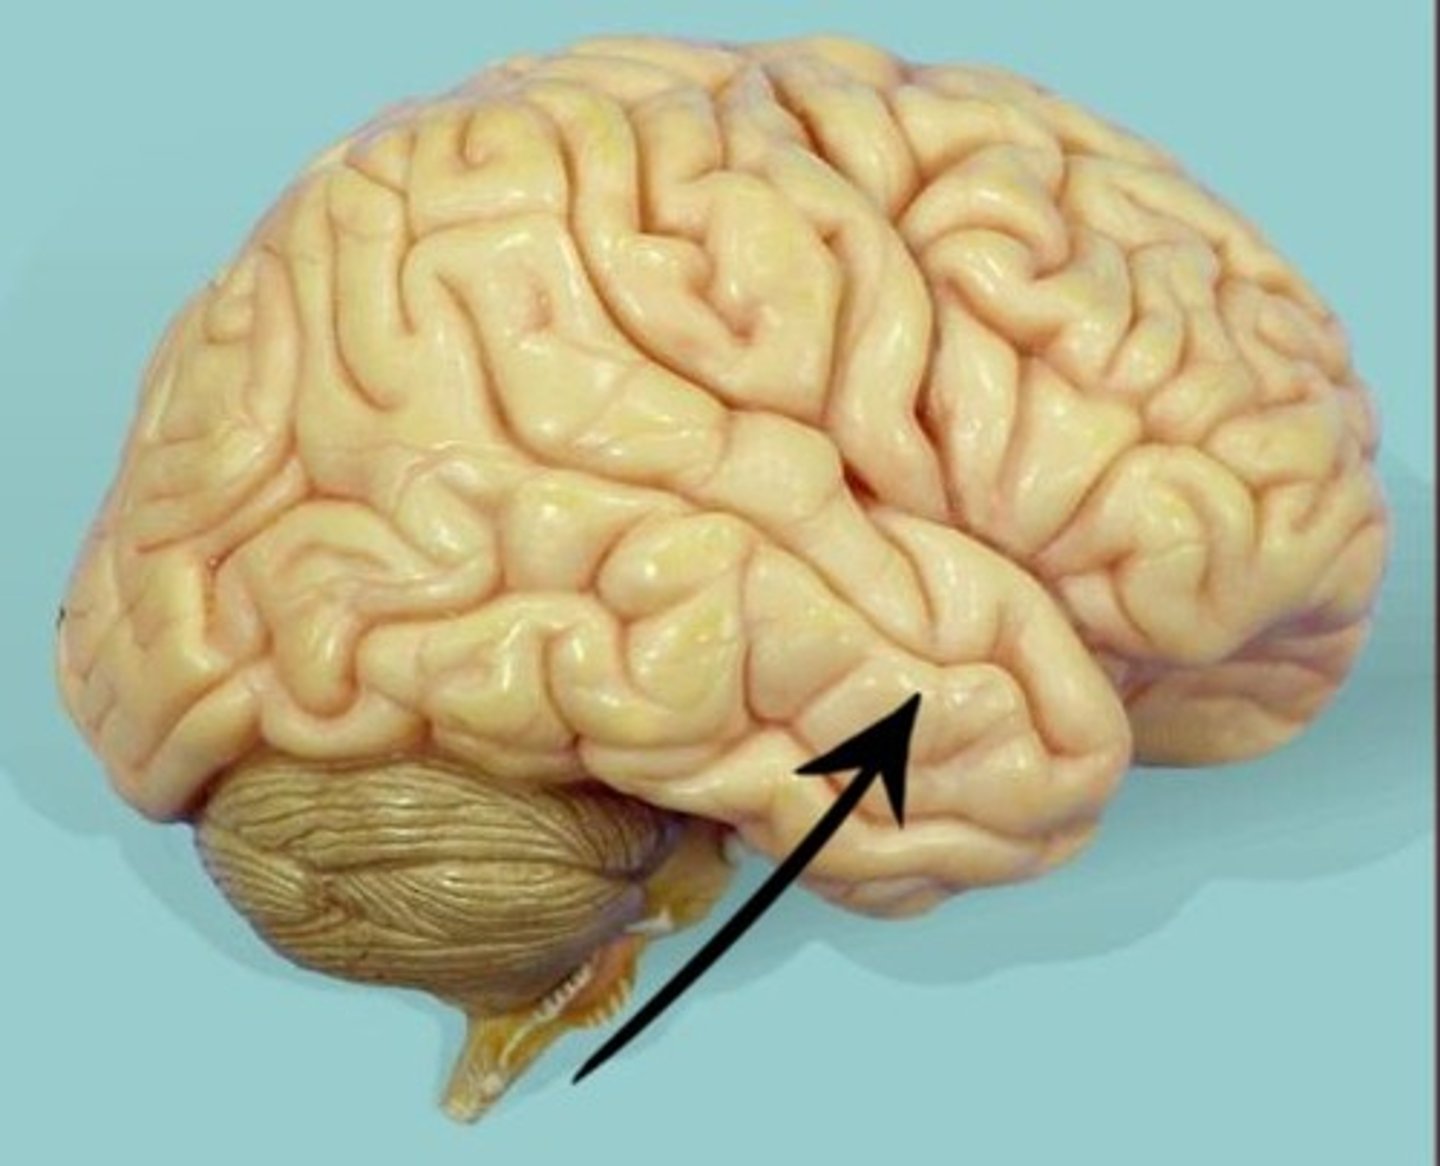

temporal lobe

lateral sulci